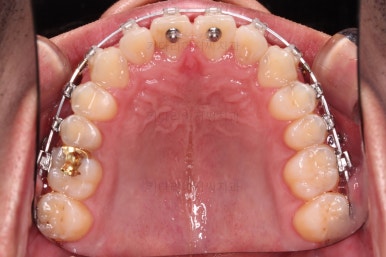

초진 시 입안의 모습입니다.

비교적 고른 편이긴 하나 아랫니가 전반적으로 밀려 나오면서 앞니끼리 부딪혀 있는 양상이고요.

어금니 맞물림도 긴밀하게 톱니바퀴처럼 위아래가 맞물려 있는게 아니라 엉성한 모습이죠.

앵글씨 3급 부정교합이라고 하는데요.

부산교정 장치를 부착했습니다.

이번에 선택하신 장치는 자가결찰 세라믹 장치에요. 스스로 철사를 묶는(결찰) 뚜껑이 달린(자가) 세라믹 성분의 장치인데요.

이번 환자분은 엠파워 클리어라고 하는 장치를 사용했으며 흔히 아신느 클리피씨와 동일한 계열의 장치입니다.

장치 부착 직후의 느낌 참고해 주시고요.